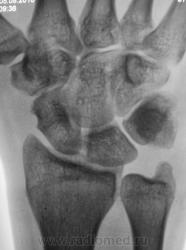

Травма месяц тому, но за помощью не обращадся. Беспокоят боли, сегодня направлен на рентгенографию лучезапястного сустава.

Перелом эпифиза луча. Не уверен насчет шилов. отростка локтевой кости. Регионарный остеопороз.

А, что за выемка по контуру ладьевидной?

Вариант основания бугорка, как бы "талия"...как по мне. И вообще - переломы в обозримом прошлом сомнительны....

Думаю, была сломана и не срослась полулунная кость. Сколько лет больному и чем он занимается по жизни?